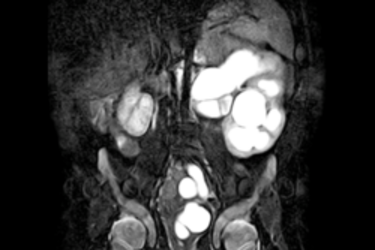

Zystische Nierenerkrankungen im Kindesalter

Uro-Magnetresonanztomographie bei Kindern und Säuglingen: In die Niere geschaut